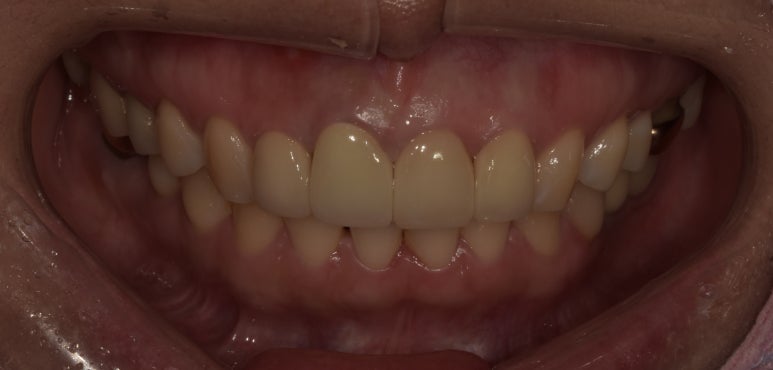

앞니브릿지교체 전후사진 비교

(전) 2023-04-10 (후) 2023-05-15

전에는 치아 사이즈가 다소 길었는데, 이번에는 약간 짧게 제작해 더 영해보일 수 있도록 했습니다.

앞으로 향후 10년 이상 문제없이 쓰실 수 있도록 스케일링과 잇몸치료도 꾸준히 받으시면서 잘 관리하실 것을 당부드렸습니다.